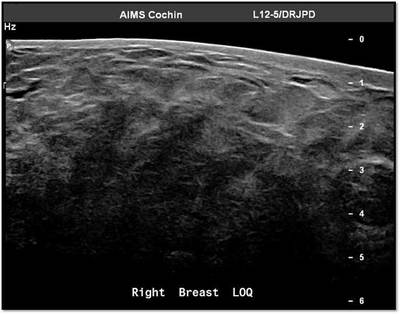

MG: Right breast shows focal asymmetric density in lateral quadrant extending for an area of 12.4 x 6.5 cm with no associated discrete mass or suspicious calcifications. Correlative ultrasound showed a heterogeneous area with echogenic vascular surrounding parenchyma in lateral quadrant with no discrete solid masses. MRI breast was performed on day 14 of LMP. Right breast shows an area predominantly consisting of fat in lateral quadrant extending for an area of 1.2×5.5x 8.9 cm along its maximum AP, ML and CC dimensions. This area is bright on fat suppressed T2 sequences and shows significant restriction on diffusion weighted sequences. There is rapid and progressive non mass enhancement in the above area extending anteriorly in to the nipple and posteriorly into the pectoralis major muscle. Two large and tortuous feeding vessels are seen to arise from the subclavian and axillary arteries respectively. Right breast shows predominantly fat containing mass showing abnormal enhancement described. The possibilities include vascular neoplasm or remotely fat necrosis. Ultrasound guided core biopsy was Suggestive of an inflammatory lesion, possibly fat necrosis. However enlarged and tortuous feeding arteries to the vascular mass was worrisome and we recommended an excision biopsy correlation. Excision biopsy showed “Multiple patchy areas of dense inflammatory infiltration in a background of fat necrosis”.